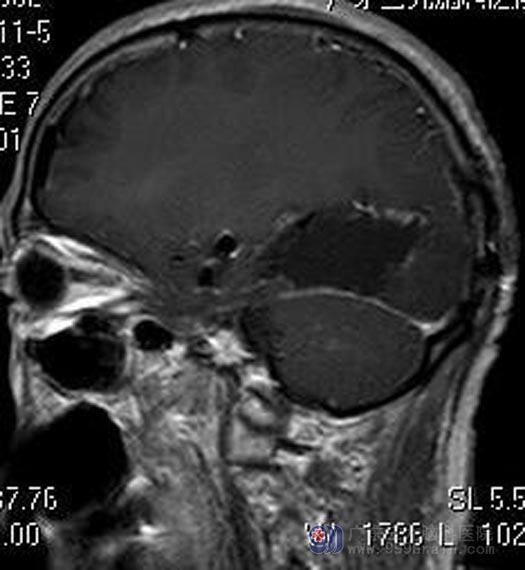

家属积极要求手术治疗。由综合神经外科鲁明主任主刀,在全麻下行左侧枕叶占位性病变切除术,术前导航计划,术中再次导航定位肿瘤位置,显微镜下见边界不清,质地混杂,部分松脆,部分质韧,全程电生理监测 ,镜下、肿瘤荧光辅助下利用超声刀分块逐步顺利全切除肿瘤。术后徐先生恢复很好,已康复出院。